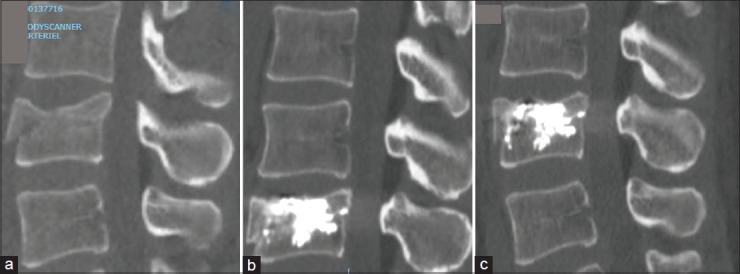

Materials and methods: Every patient who sustained a posttraumatic thoracolumbar vertebral fractures treated by SJPVBA from the January 6, 2012, to January 6, 2020, was retrosepctively included. The main outcome measure was the height of the vertebral body (anterior/middle/posterior parts) on the sagittal computed tomography scan. The secondary outcome measures were a 11-point Likert scale for the pain and the Oswestry Disability Questionnaire for the quality of life. All the data were compared at different times: preoperative versus day after the procedure versus at least 3 months versus (if disposable) a long-term special consultation just before the publication.

Results: SPJVBA is a simple, quick (52-min-long on average) reliable, efficacious method to significantly improve the vertebral height (+3.5 mm and 4.3 mm of the anterior and middle vertebral heights, P < 10-5), to correct kyphosis and relieve pain (-6.5/10 on the Likert scale for pain). We also showed that there is a significant vertebral height decrease between day 1 (-2.1 mm and - 0.7 mm of the anterior and middle vertebral heights, P < 10-5 and 0.005, respectively) and 3 months but not between 3 months and the last consultation with a mean follow-up of 37 months (-0.1 mm and - 0.2 mm of the anterior and middle vertebral heights, P = 0.277 and 0.4289, respectively).